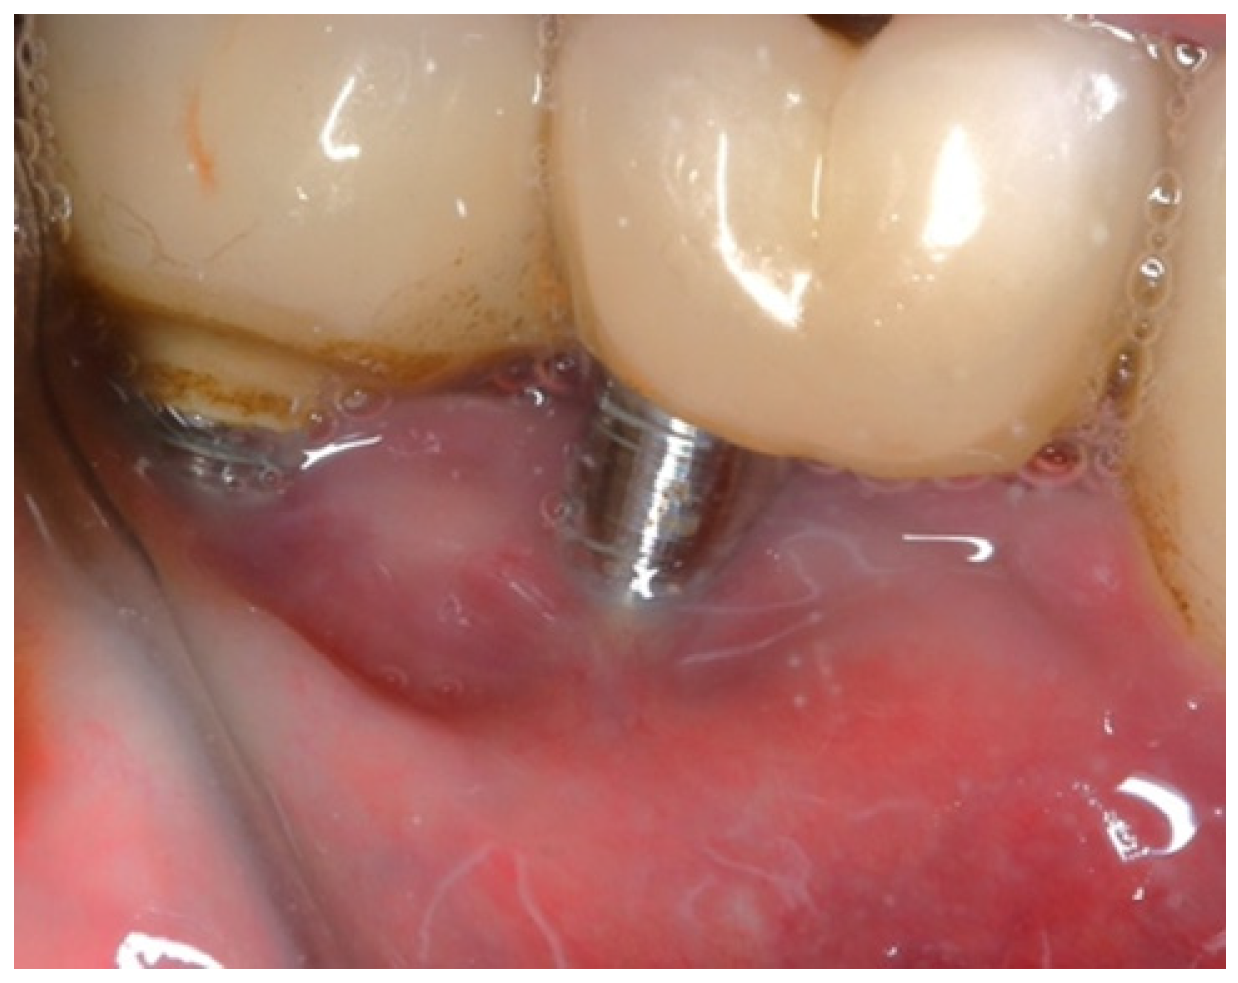

An 80-year-old male patient presented at the private dental office with severe mandibular pain, swelling, and mobility of a dental prosthesis retained by implants. The chief complaint was the lack of stability and mobility in mandible rehabilitation, with the symptoms already described. The medical history included controlled hypertension, hypercholesterolemia, anticoagulant therapy, and a history of heavy tobacco use, which ceased 15 years prior to the oral rehabilitation. The clinical examination revealed inadequate oral hygiene, extensive fixed-prosthesis and dental implant mobility, with PDs exceeding 10 mm; significant BoP was found, and severe vertical bone loss was radiographically confirmed around implant #33, #36, #37, #41, #43, #44, and #47 (Figure 16).

The same protocol mentioned above was used. A five-day antibiotic regimen was administered prior to the surgical procedure. At the surgery, the site had no suppuration and minimal BoP; the implants #33, #36, #37, #44, and #47 were removed, and new implants were placed to provide a new rehabilitation. For the site #41 (without mobility and severe bone loss), following prosthesis and abutment removal (Figure 17a,b), a BSF with two crestal extensions was made around the implants (Figure 17c,d), facilitating optimal access and flap management during the surgical procedure, eliminating the need to retract two flaps, as a midcrestal flap requires. The flap was retracted lingually; the granulation tissue was removed, and the contaminated implant surface fully exposed (Figure 17d).

Figure 17. Step-by-step treatment for peri-implantitis using the iMPACT and Quadrant protocol. (a) Initial clinical evaluation; (b) Removing the abutments for peri-implantitis treatment; (c,d) BSF raised for implant exposition; (e) Insertion of the hinge (pin), which was crewed into the implant; (f) Hinge in position; (g,h) iMPACT adapted to the hinge; (i) iMPACT spinning for implantoplasty; (j) The implant surface was smoothed, and bone around the implant was gently cut (osteotomy); (k) occlusal view showing the osteotomy; (l) implantoplasty finished—implant surface is completely smoothed (machined); (m) Bone graft; (n) Suture and abutments were repositioned.